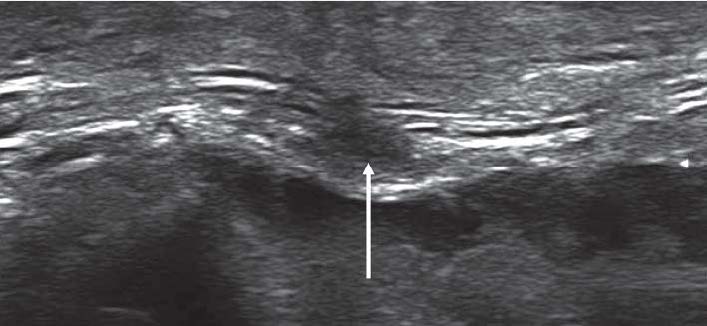

Мы объединили 11 (36,7%) пациентов с внутриствольными повреждениями при закрытой травме в одну группу с 19 (63,3%) пострадавшими с аналогичными изменениями при открытой травме. Всего у 30 пациентов с внутриствольными повреждениями нервов определялись следующие ультразвуковые признаки изменения нервных стволов: у 83,3% больных – снижение эхогенности нервного ствола, в 76,7% случаев – увеличение диаметра нерва, 56,7% – неровные и нечёткие наружные контуры, в 86,7% случаев – отсутствие чёткой внутренней дифференцированной структуры нерва (рис. 3).

Рис. 3. Продольная эхограмма тракционного повреждения общего малоберцового нерва (метки) на уровне подколенной ямки с наличием диффузного утолщения нервного ствола и потерей волокнистой внутренней структуры